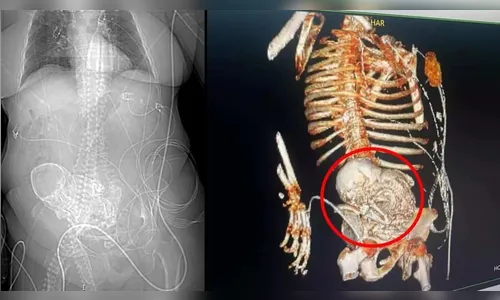

Autor A idosa não resistiu e morreu após o procedimento de retirada do feto - Foto: Reprodução

Devido à suspeita, os funcionários da instituição de saúde realizaram uma tomografia 3D na paciente, onde foi descoberto que na verdade havia um feto calcificado no abdômen da mulher.